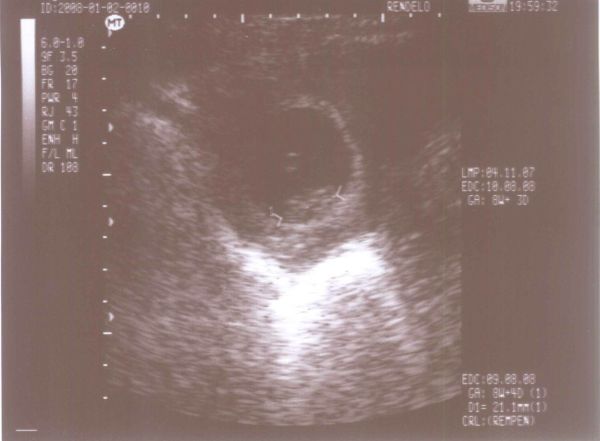

Kérdés: Ti hogy álltok a vércsoportal? Ma mentem a vérképemért, és azt írták negatív vagyok, bár én most ebben kételkedem mert emlékeim szerint pozitív, de ha én tévedek akkor egy kicsit el kezdek aggódni, ne hogy gondd legyen ez a későbbiekben.